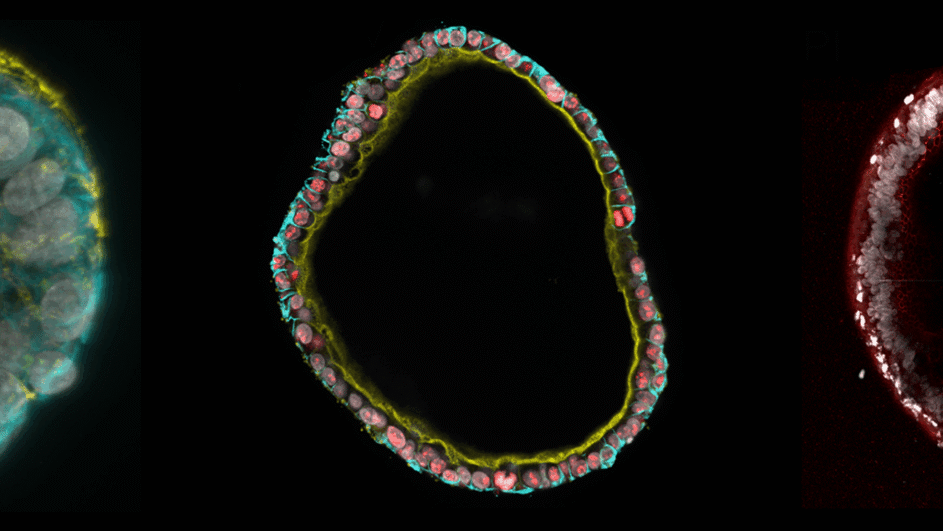

The Hubrecht Institute and Radboud University created an animal-free synthetic gel that supports long-term and robust growth of 3D organoids.